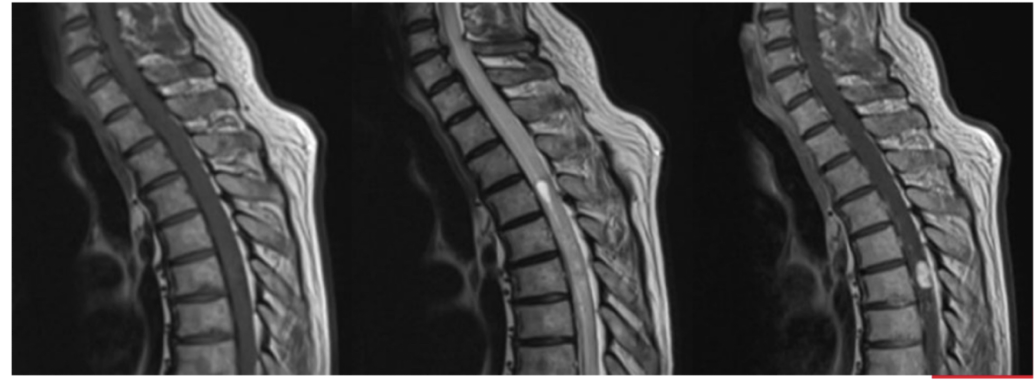

Sequence + Pathology?

T1,T2

• Cauda Equina syndrome

• L5/S1 disk space herniation compressing the cauda equina.

• Signal intensity is lost in T2 sag as you get to L5/S1 disk space.